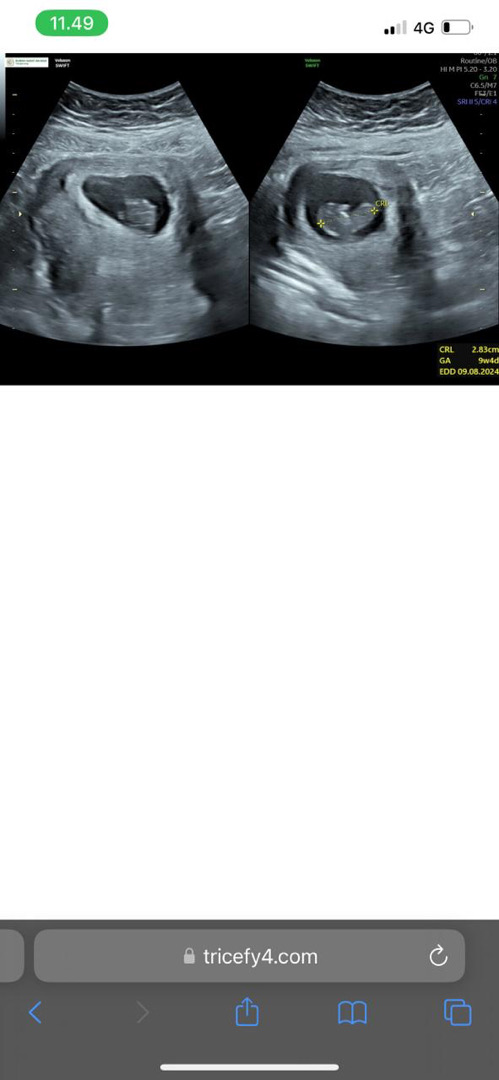

Usia kandungan ber ubah2 saat hamil tm1

Bun ada yang sama ga . Udah usg ke 3 kali karna sering banget keram dan flek. Nah awal bagus bagus aja saat usg hitungan hpl nya maju terus . Tiba tiba usg kembali . Harus nya usia kandungan 10 minggu berdasarkan hitungan minggu sblm nya usg . Tapi ini jadi cuma 9minggu 4 hari . Kurang 3 hari dari itungan nya . Normal ga ya bun??

Kalo USG itu usia kandungan di hitung berdasarkan baby nya bun, kalo yg kita biasanya bilang HPL itu kan dari HPHT, jadi wajar kalo hasil usg usia kandungan beda terus.

Kalo minggu2 awal emg masih suka brubah2 bund usia kandungannya Nanti makin tambah makin akurat kokk